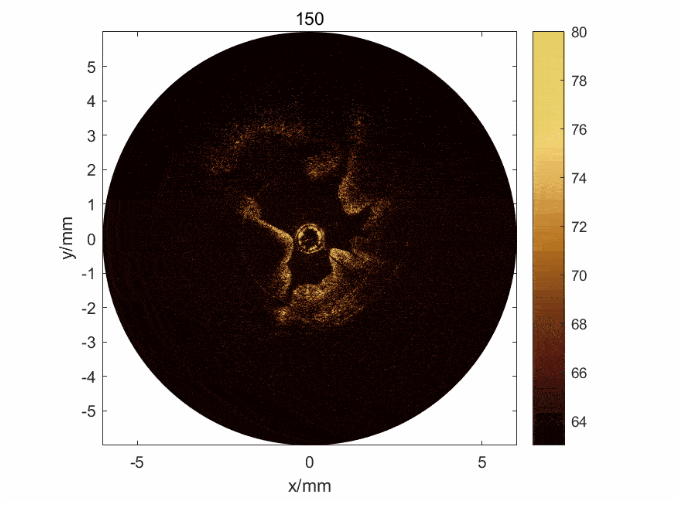

圖1: 新西蘭大白兔子宮在超聲模態(tài)(上)與OCT模態(tài)(中)下的橫截面圖像及子宮內膜三維展開圖(下)

針對這一臨床問題,研究團隊開發(fā)了一種基于OCT/超聲的雙模態(tài)內窺成像系統(tǒng)。該系統(tǒng)可以獲取整個子宮內膜、從表面到深層的三維信息,其中OCT可以實現(xiàn)內膜的精細成像,超聲可以實現(xiàn)內膜的整體成像;并且基于該系統(tǒng),實現(xiàn)了對子宮內膜損傷的量化評估分析。

在子宮內膜損傷模型兔中,該雙模態(tài)內窺系統(tǒng)實現(xiàn)了世 界上首 個小動物活體內窺成像,并區(qū)分了健康和受傷的子宮內膜組織。而量化評估分析的結果進一步證明,結合兩種模態(tài),相對單個模態(tài),明顯提升了對內膜損傷評估的準確性。本工作論證了該技術用于評估子宮內膜容受性的價值,并展現(xiàn)出應用于生殖健康以及診斷子宮其他疾病的臨床潛力。

圖2: a) 子宮內膜損傷模型兔的OCT/超聲圖像及其圖像分割和量化方法; b) 通過雙模態(tài)獲取的信息可以判斷子宮內膜的損傷程度,驗證了雙模態(tài)的必要性